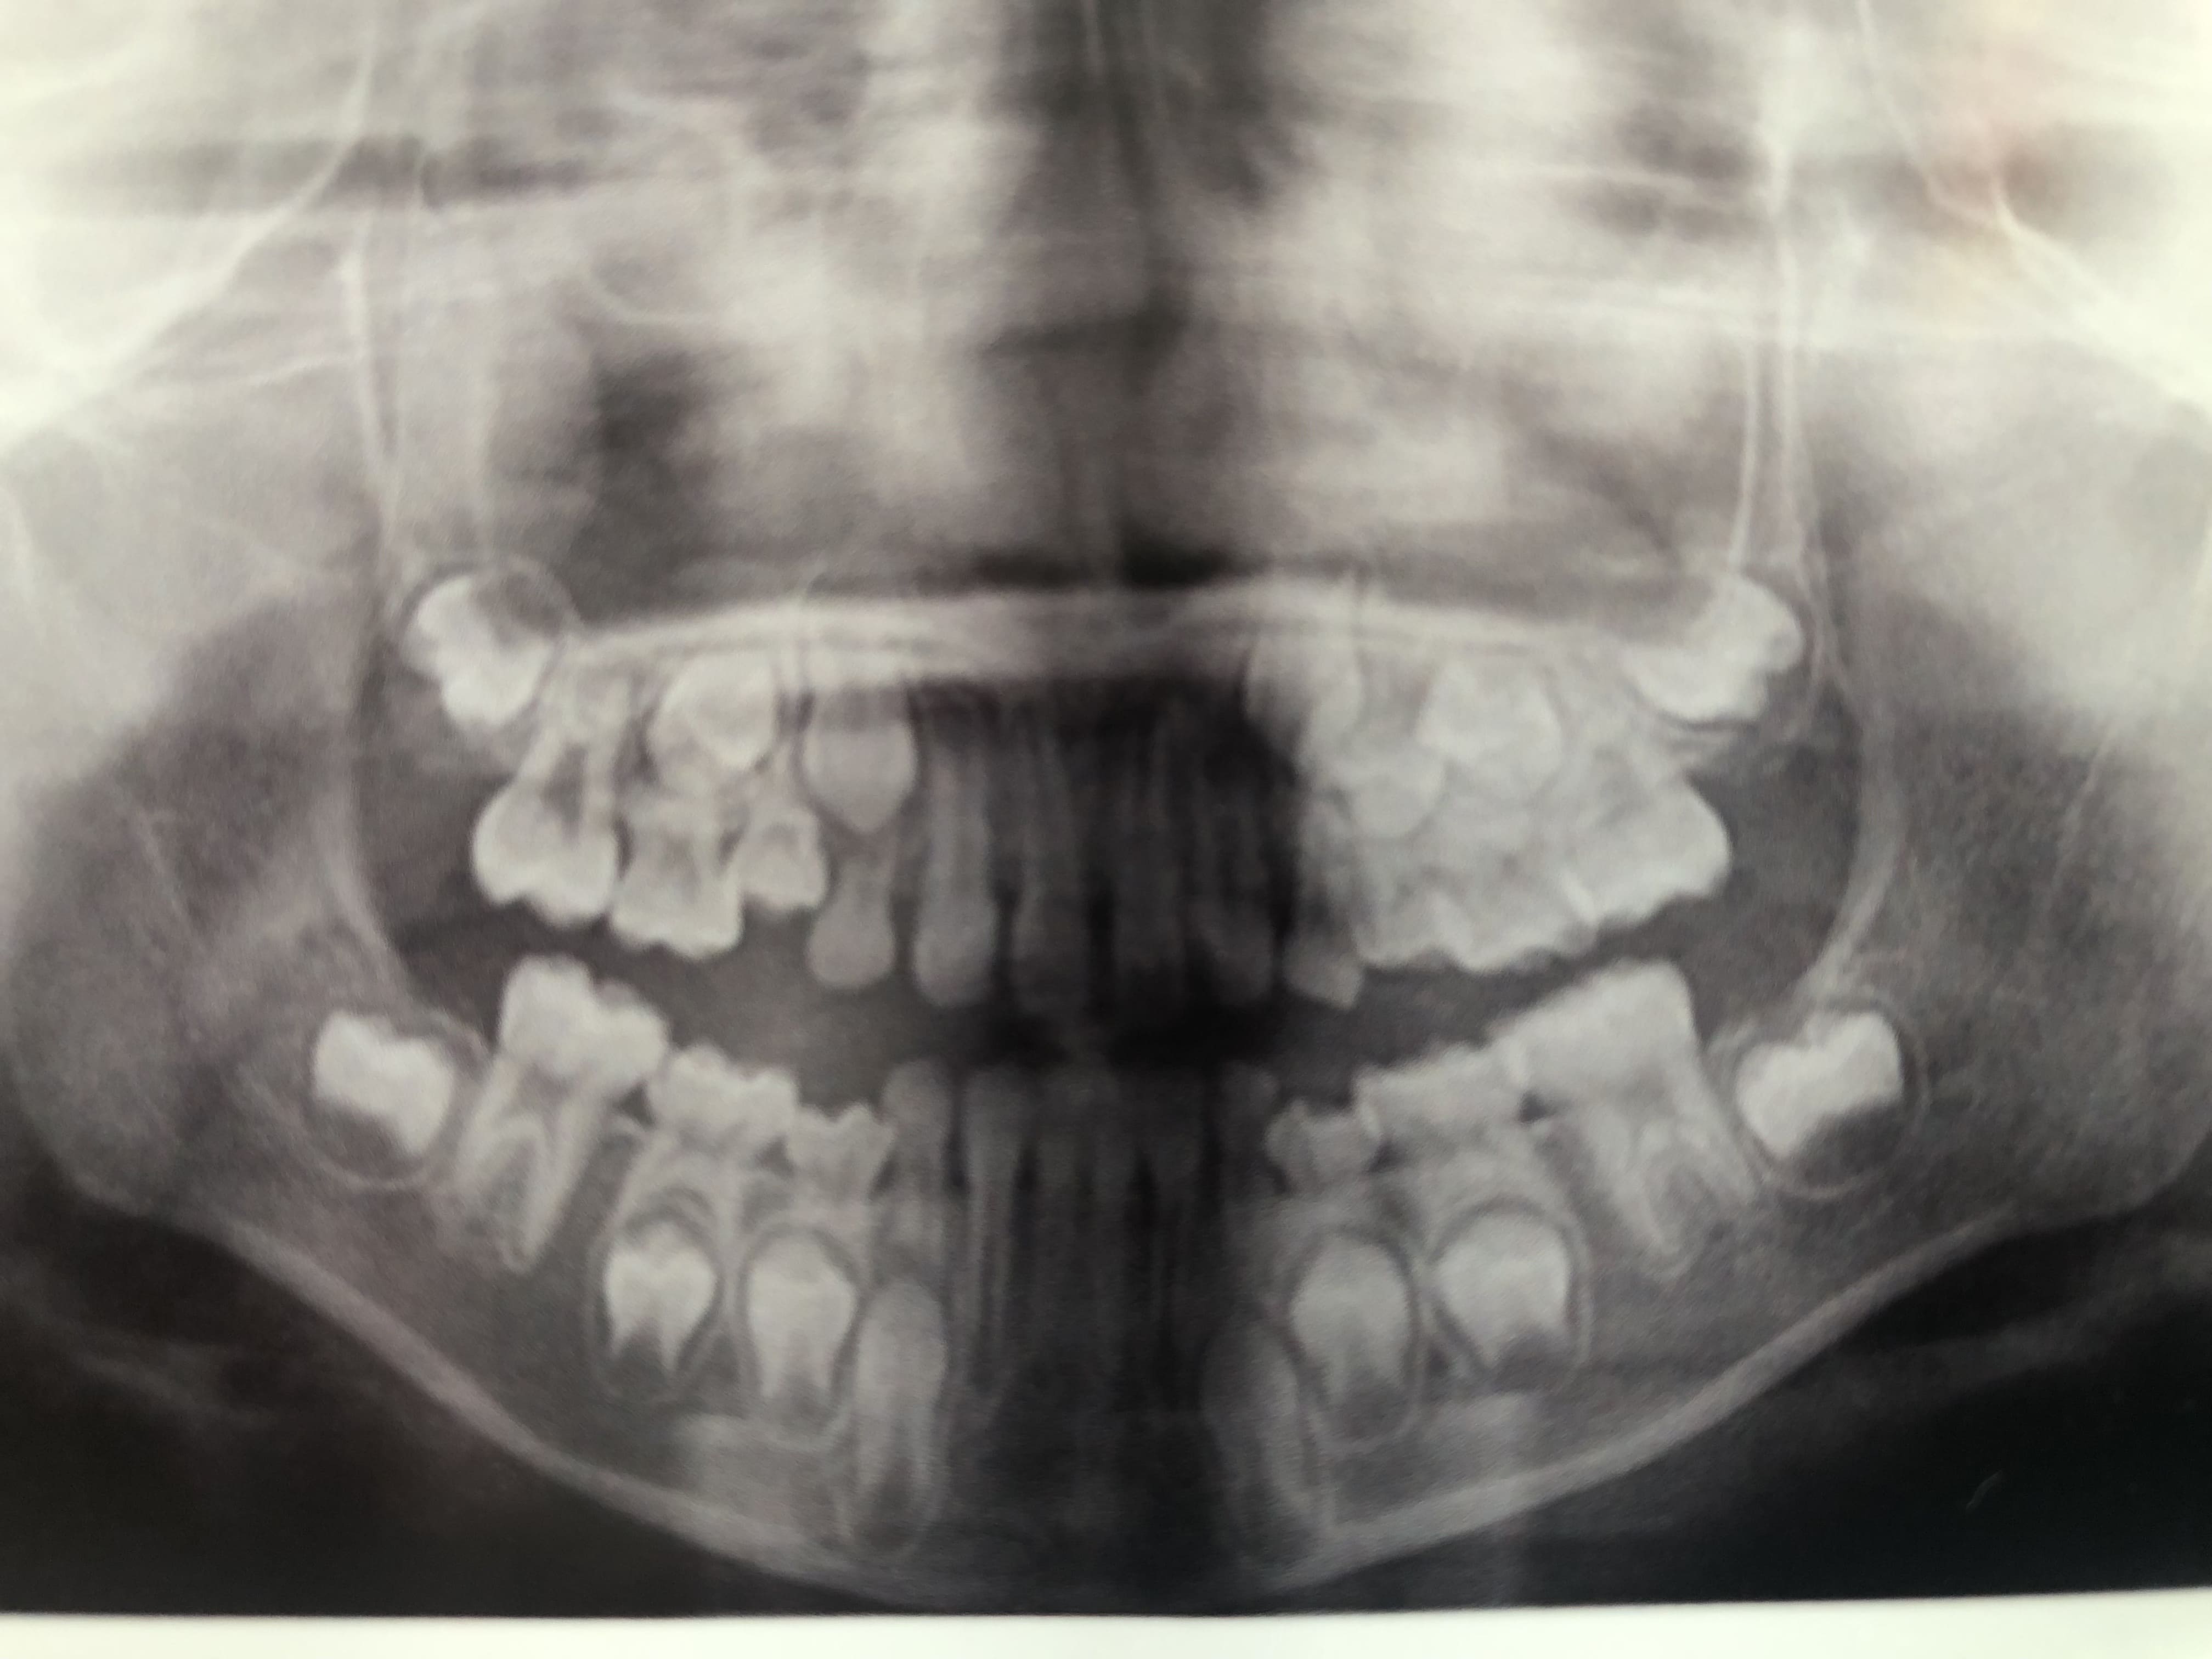

先日、9歳女子がパノラマ写真を撮影した際に犬歯がやや内側(舌側)に位置しているように見えるため、萌出スペースの不足が懸念されます。

と言われ高位・異所萌出の兆候ありと診断されました。

外観上は結構隙間があるのですがこのパノラマから萌出スペースの不足で異所萌出の兆候はありそうですか?

レントゲンから伺えることは左上の3番のスペース不足があるかもしれないという事です、ただこの時点のパノラマレントゲンで診断するのは時期尚早です、左上4番が生えるまで待つのがいいと思います。